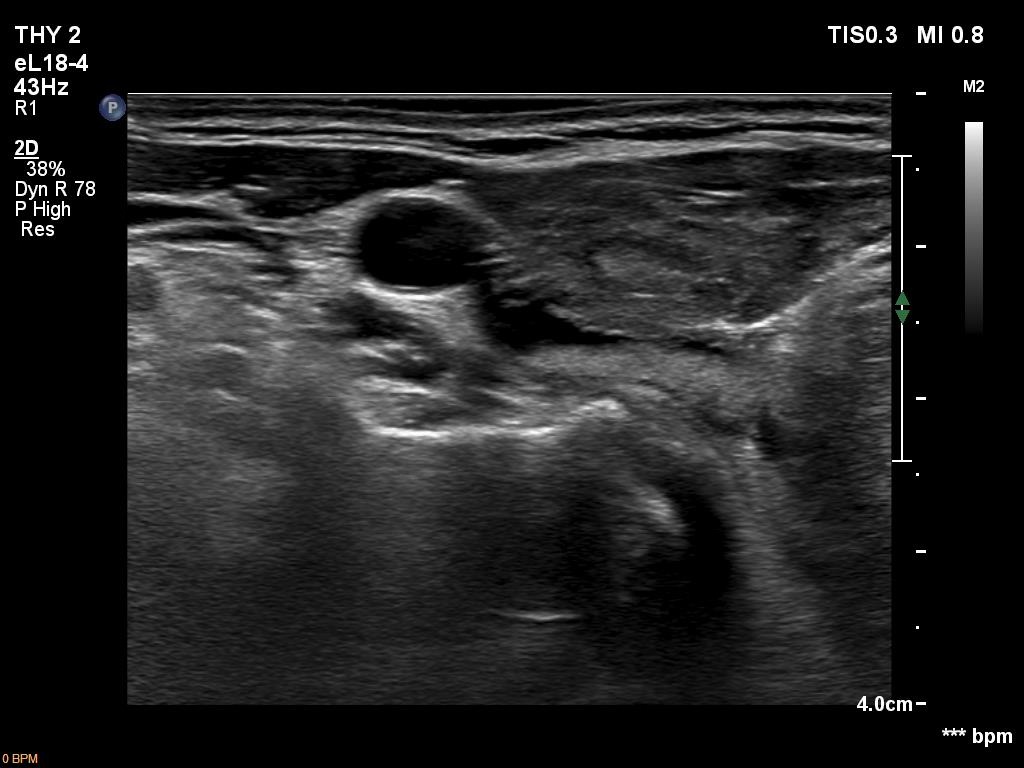

Ultrasonography. The thyroid was hypoechoic and presented several more hypoechoic and echonormal islets corresponding to the underlying thyroiditis. There was a mixed, dominantly cystic mass dorsal to the lower two-third of the right lobe. The lesion has echonormal solid part and showed intracystic echogenic figures.